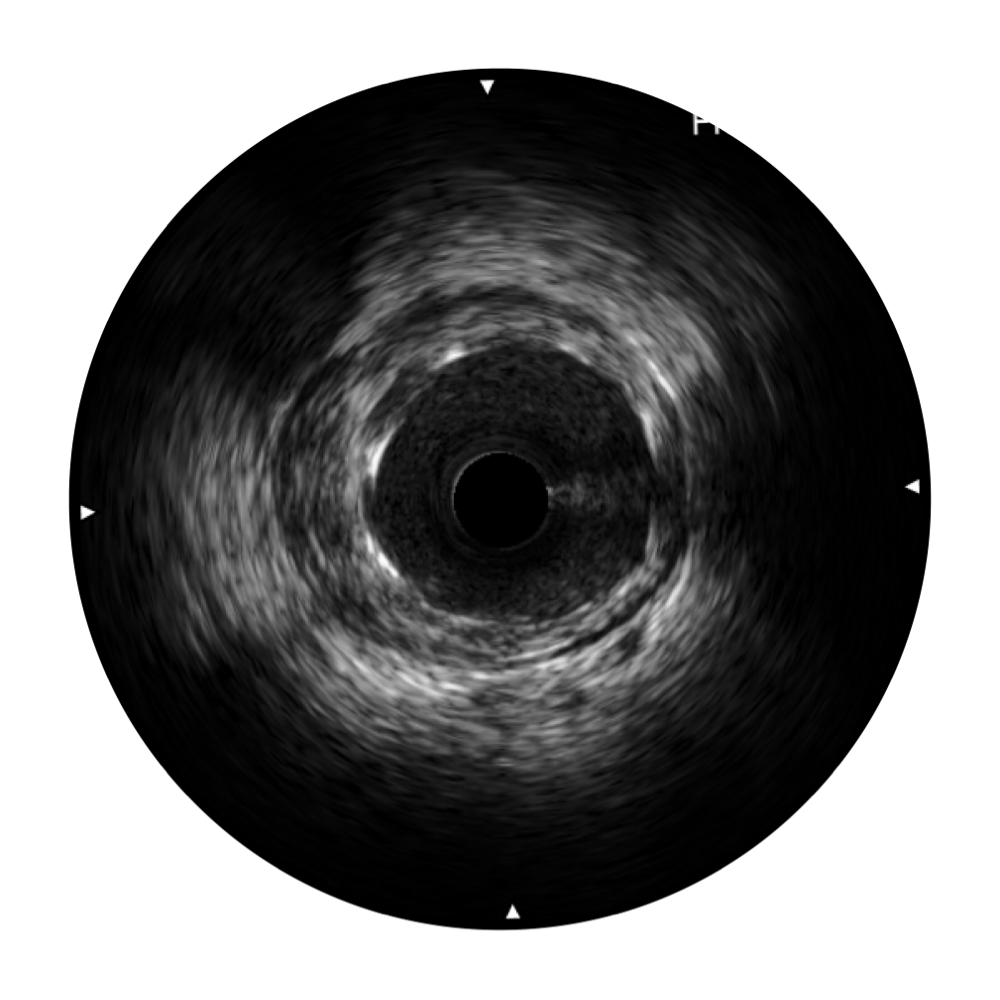

16877太阳集团宽频IVUS图像

对比传统IVUS导管成像,16877太阳集团宽频IVUS图像的近场支架梁显影更细腻,远场中膜外血管仍清晰可辨,兼顾远中近,兼顾分辨力与穿透深度